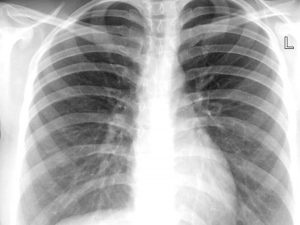

Caso medico più unico che raro riportato dalla National Library of Medicine: una donna, forse per imbarazzo, ha nascosto l'inalazione del preservativo fino a che il verificarsi di pesanti sintomi, in un primo momento erroneamente associati alla tubercolosi, ha fatto emergere la verità.